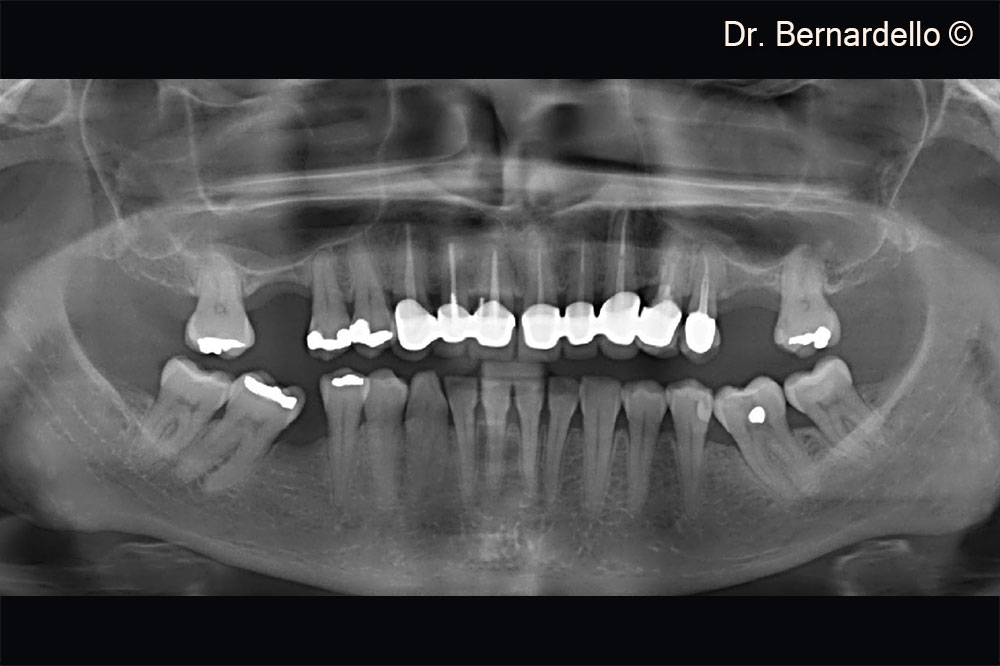

Dựa trên chiều rộng xoang, bệnh nhân nữ (55 tuổi) được coi là đủ điều kiện để thực hiện phẫu thuật nâng sàn xoang qua mào xương.